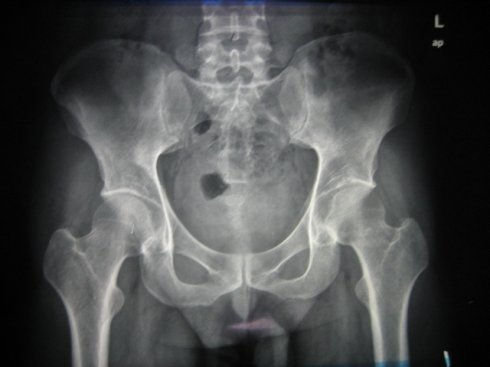

上面两张图片,是同一位患者在手法调整前后的片子。

大家别弄错了,上面一张是治疗前的,下面一张是调整后的。

显然,出现了很大的问题。原本左右高低不甚显著的骨盆,在手法调整之后,骨盆严重倾斜。

即使是没有受过医学教育的患者也能看出结果 ---- 病情经治疗后更加严重了。